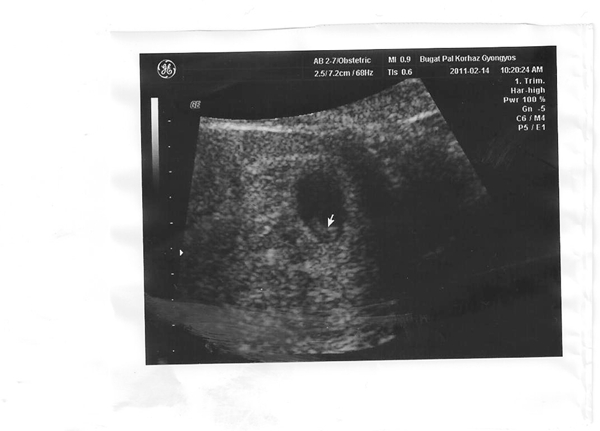

Melinda: juhéééé, én úgy örülök... Mit érzel, mi lesz?Mit szeretnétek....?